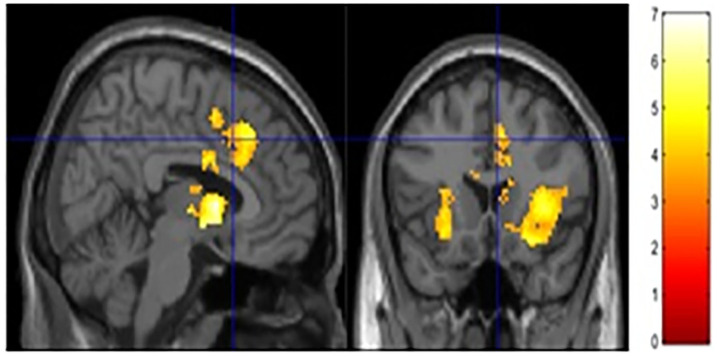

The current study focused on activation related to risk-taking. Risk-taking was examined by parametrically modulating the decision to inflate with the probability of balloon explosion. An analysis of activation related to risk taking behaviors collapsed across both groups showed significant activation in regions typically associated with risky decision making and reward seeking, such as the dACC, NAc, and insula (see Figure 2 and Table 3). However, no significant group differences were observed after correcting for multiple comparisons (see Supplementary Material for other analyses).

Table 3: fMRI activation.

| Region | BA | k | z | x, y, z |

|---|---|---|---|---|

| R. Ventral striatum | 2,191 | 5.33 | 6, 8, 4 | |

| R. insula | 13 | 5.09 | 36, 22, 4 | |

| Anterior Cingulate | 32 | 456 | 4.75 | 8, 28, 42 |

| R. Ventral striatum | 307 | 4.53 | 14, −14, 20 | |

| R. Insula | 13 | 256 | 4.38 | 34, −36, 24 |

| L. Insula | 13 | 434 | 4.27 | −28, 22, 0 |

| L. Insula | 13 | 177 | 4.16 | −28, −34, 38 |

| R. Precentral | 4 | 182 | 4.13 | 26, −16, 42 |

Effective Connectivity